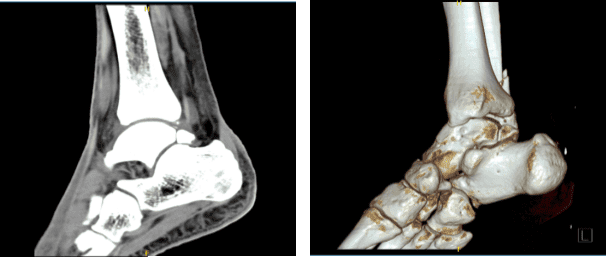

CT-scan presented and reviewed; Bones are normally mineralized without a focal osseous lesion. There is a ununited obliquely oriented fracture of the distal fibula meta diaphysis extending to the level of the lower syndesmosis just proximal to the tibial plafond.

Distal fracture fragment measures 4 cm in length and is slightly posteriorly and laterally displaced less than 2 mm. There is no significant angulation. No other fractures are seen. There is a large os trigonum posterior to the talus with degenerative changes at the synchondrosis.

Ankle mortise is not widened. Talar dome is smooth without an osteochondral lesion. There is no tibiotalar joint space narrowing. Faint calcifications are seen along the lateral ligaments and within the lateral joint recess.

Mild chondrocalcinosis. There is no joint effusion. CT is suboptimal to evaluate the ligamentous complexes of the ankle.

There is mild narrowing of the posterior subtalar and talonavicular joints. Limited evaluation of the midfoot is unremarkable. Limited evaluation of flexor and extensor tendons are unremarkable. The Achilles tendon shadow is grossly unremarkable.

The unenhanced musculature is normal. Slightly displaced obliquely oriented fracture of the distal fibula extending to the lower syndesmosis just proximal to the tibial plafond Faint calcifications along the region of the lateral joint recess and lateral ligamentous favors mild chondrocalcinosis.

CT Right ankle non-contrast